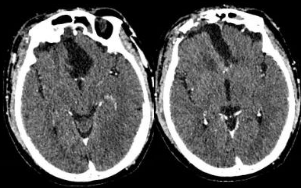

术后CT